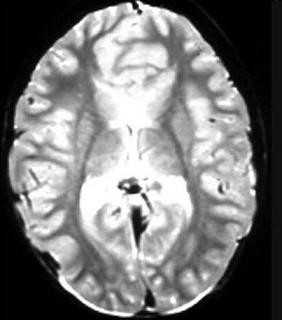

问题 根据MRI表现,考虑是何种先天性神经系统异常的疾病是 ( )

选项 A、灰质异位症 B、胼胝体发育不全 C、Dandy-Walker综合征 D、前脑无裂畸形 E、脊柱裂 单选题

答案 D